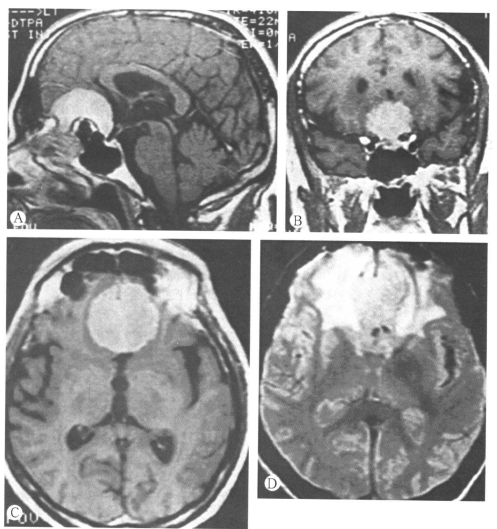

59岁男性嗅沟脑膜瘤患者,3年来轻度人格改变和智能障碍。磁共振:A.矢状位(T1)增强像:中线平面显示肿瘤的前后和上部范围。有一种不常见的骨质改变,气窦向颅底肿瘤扩展。肿瘤的后下缘位于鞍结节下,双侧视神经间。肿瘤的后表面有脑脊液池。肿瘤的前下缘侵犯筛板区。B.冠状位(T1)增强像:肿瘤后缘平面显示肿瘤片位于双侧颈内动脉间视神经上。其他冠状位像显示肿瘤外侧部没有侵入气窦。C.轴位(T1)增强像:确定肿瘤的外侧边界。肿瘤周围有水肿或胶质反应。D.轴位(T2)未增强像:确定肿瘤邻近组织的水肿范围。大脑前动脉的A2段邻近肿瘤包膜。术中将大脑前动脉A2段从肿瘤包膜上后部通过薄层胶质组织分离开,在后部包膜的中部,动脉位于脑脊液池中,有小动脉分支硫松附着于肿瘤包膜。全切除肿瘤,病人完全恢复。